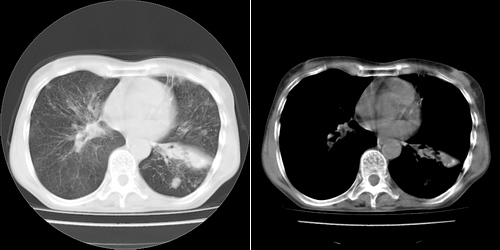

以下是引用lihuuuu在2006-7-18 18:16:00的发言:[br]支持肺结核诊断[br]本病例符合结核“三多”“三少”特征(多病灶、多形态、多钙化、少肿块、少堆积、少增强)中的前五个特征,另外左下叶背段有不张样改变-考虑伴有支气管内膜结核所致段不张。

以下是引用yang4132在2006-7-18 10:04:00的发言:[br]两肺多发 多形态病变,部分半纤维条索和斑点壮钙化,胸膜肥厚粘连,考虑结核。